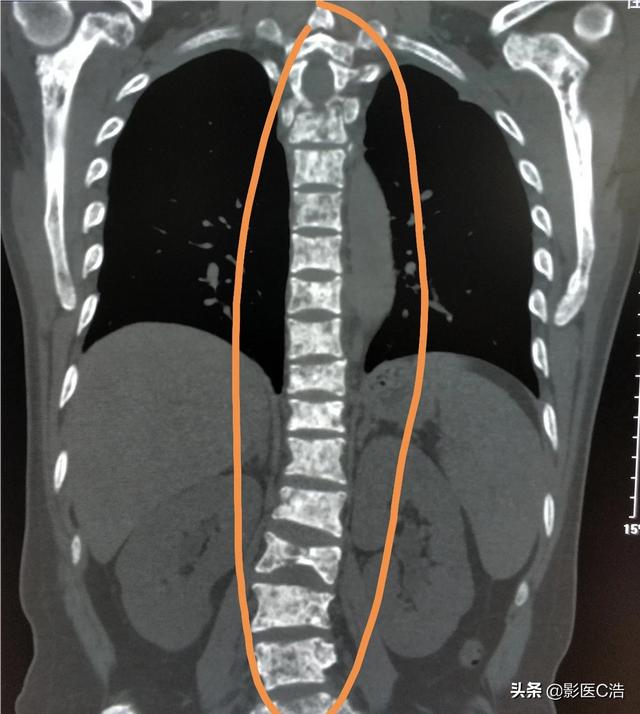

骨転移はどのような痛みに注意すべきですか?骨転移は悪性腫瘍の末期によく見られる症状で、体の他の部位にある原発腫瘍が血液やリンパ液の経路を通って骨に転移し、骨転移を形成することを指します。骨転移は、正常な骨組織が破壊され、腫瘍組織に置き換わっていることを示す。骨転移は病変の特異性により、溶骨型、造骨型、混合型の3つに分類される。骨転移の好発部位は中軸骨(脊椎、骨盤)、肋骨、下部骨幹部で、特に中軸骨が最も多く、これはこの部位の血液供給の特徴と関係しています。下の円のように骨転移が多発し、脊椎の状態が悪い。

- 癌患者の骨転移は、比較的好発部位が多い。脊椎>骨盤>下肢の長骨、肋骨>頭蓋骨>上肢の長骨である。

がんの骨転移の好発部位